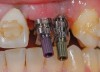

The chief complaint of a 48-year-old woman who presented to her restorative dentist was, “I don’t like the way my implant looks” (Figure 1). This implant had been placed by a previous periodontist and restorative dentist. The patient is now seeking a second opinion. In evaluating this case upon referral to the periodontist, a reddened appearance of the gingival and mucosal tissue encompassing almost the entire facial aspect could be observed. In addition, the radiographs demonstrated a 5-mm diameter implant in place with a deciduous cuspid in the place of No. 11. Deep probing depths were noted around the facial aspect of the implant, and threads could be detected under the tissue.

In evaluating the options, it was decided that the implant placed was too large and that the deciduous cuspid site could be used for a single implant as an abutment for a cantilevered pontic to restore the missing lateral incisor in a more esthetic manner. The goal the treatment was to augment the lateral incisor site in order to bring the facial tissue level more coronal (Figure 2 through Figure 11).